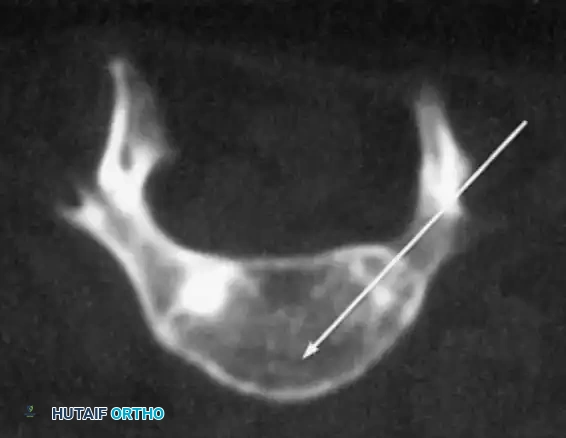

* Advanced Imaging: MRI is mandatory to evaluate for hydromyelia, tethered cord, diastematomyelia, and Arnold-Chiari malformations. Intravenous pyelography or renal ultrasound should be updated per urological recommendations to map ureteral anatomy prior to anterior spinal approaches.

Pedicle screw fixation is the anchor of choice, providing three-column control even in the absence of posterior elements. Free-hand techniques are often supplemented with intraoperative fluoroscopy or robotic navigation due to the highly dysmorphic pedicle anatomy.